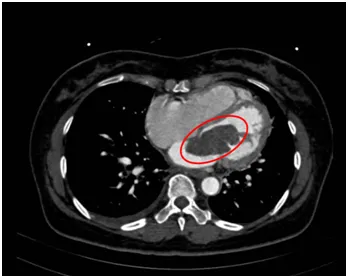

Ảnh chụp MRI phát hiện khối u nhầy trong tim người bệnh H. Ảnh: HL

Bà HTTH (54 tuổi, sống ở quận 6, TP.HCM) đến khám tại bệnh viện trong tình trạng khó thở, cảm thấy hồi hộp. Qua siêu âm, các bác sĩ phát hiện có một khối u lớn trong tim lấp gần hết lỗ van hai lá, gây cản trở dòng máu qua tim đi nuôi cơ thể.